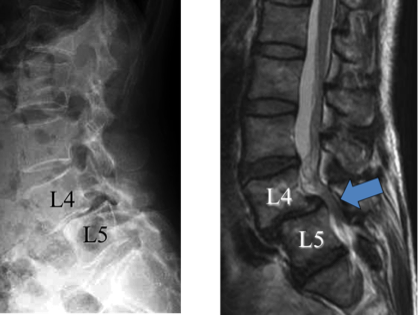

脊椎脊髄センター | 総合東京病院【公式】中野区 練馬区 24時間, 腰椎変性疾患 | 総合東京病院【公式】中野区 練馬区 24時間救急受入,

腰椎変性疾患 | 総合東京病院【公式】中野区 練馬区 24時間救急受入, 脊椎脊髄疾患について・主な疾患 | 一般社団法人 日本脊椎脊髄病,